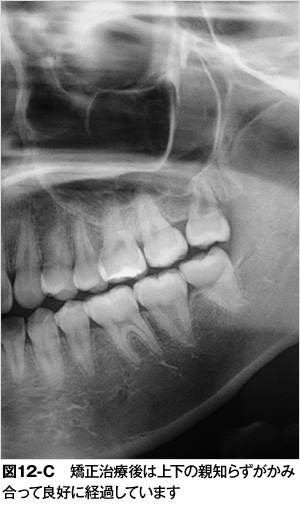

| 5. | 矯正治療で親知らずを正しい位置に動かすことができる:親知らずの生える方向が悪くても矯正治療によりきちんとかめるように治すことができます。写真は上顎の親知らずの生える方向が通常よりも前方に向いてしまったために手前の第二大臼歯に接触し、親知らずがこれ以上生えられない状態です。(図12-A)親知らずの生える場所が十分にあり、下顎にかみ合うべき親知らずも正常に生えているので、上顎の親知らずを矯正治療で移動させました。(図12-B)矯正治療後は上下の親知らずがかみ合って良好に経過しています。(図12-C)矯正治療は歯を動かす治療ですがどのような状況でも可能とは限りません。矯正治療で治せるかどうかは歯科医師に相談することをお勧めします。 |

矯正治療で親知らずを正しい位置に動かすことができる:親知らずの生える方向が悪くても矯正治療によりきちんとかめるように治すことができます。写真は上顎の親知らずの生える方向が通常よりも前方に向いてしまったために手前の第二大臼歯に接触し、親知らずがこれ以上生えられない状態です。